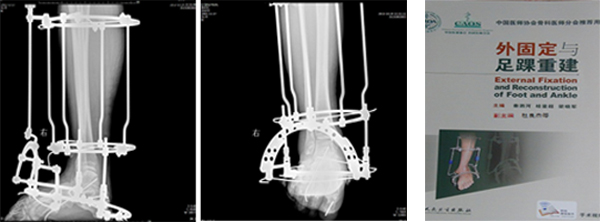

3、神经系统损伤后的下肢功能重建

下肢畸形是脑、脊髓、周围神经等损伤后常见的并发症,严重影响患者生活质量,杜良杰教授带领团队开展了大量下肢矫形功能重建手术,使大量患者的站立和行走功能得到了显著提高。杜良杰主任作为副主编参与《外固定与足踝重建》的编写,该书成为中国医师协会骨科医师分会推荐用书。

大龄脑瘫患者双下肢畸形分期 大龄脑瘫患者双下肢畸形一期矫正

矫正外固定架固定术 外固定架固定术

脊髓损伤后下肢痉挛马蹄内翻足畸形矫形术后 杜良杰教授参编专著(副主编)

脑外伤后下肢痉挛性马蹄内翻足矫正术后 髌骨脱位马蹄内翻足矫形术后